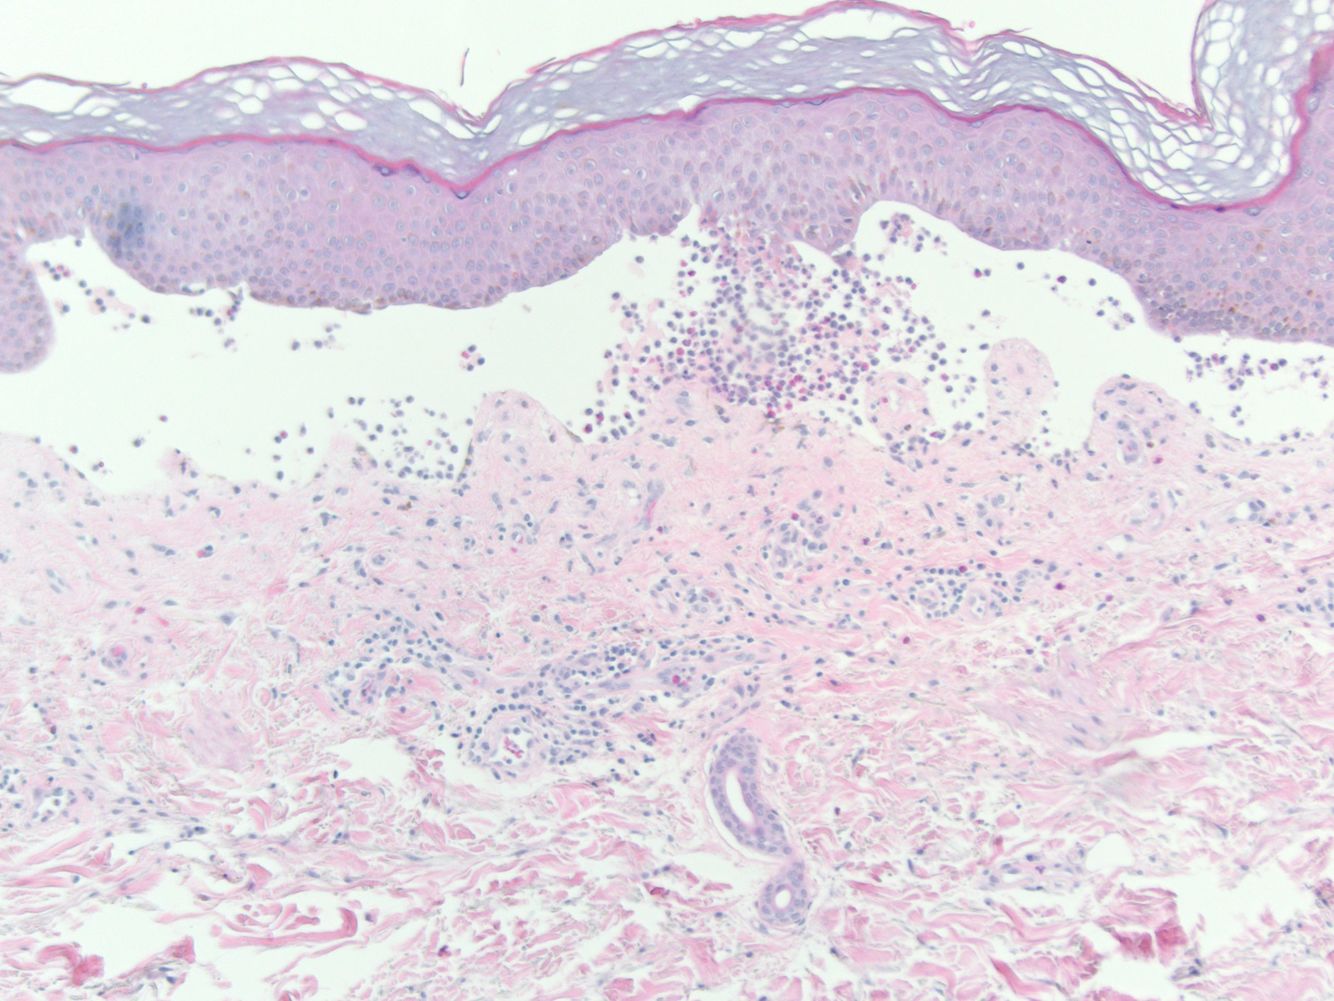

What is this a histology section of?

Psoriasis